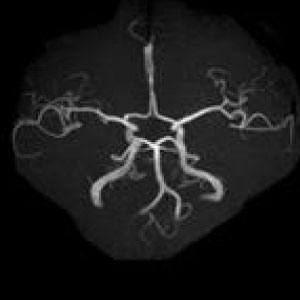

MRIはMagneticResonanceImageの略で強い磁石と電波によって人体の構造を見ることが出来る検査です。

頭部領域から脊椎・関節・骨疾患、腹部に至るまで全身部位の診断に役立ちます。

脳梗塞、脳腫瘍、脳動脈瘤、頚髄症、椎間板ヘルニア、脊柱管狭窄症、脊椎圧迫骨折、腱板損傷、各関節靭帯損傷、半月板損傷、骨壊死、肉離れ、骨腫瘍、軟部腫瘍、炎症、など